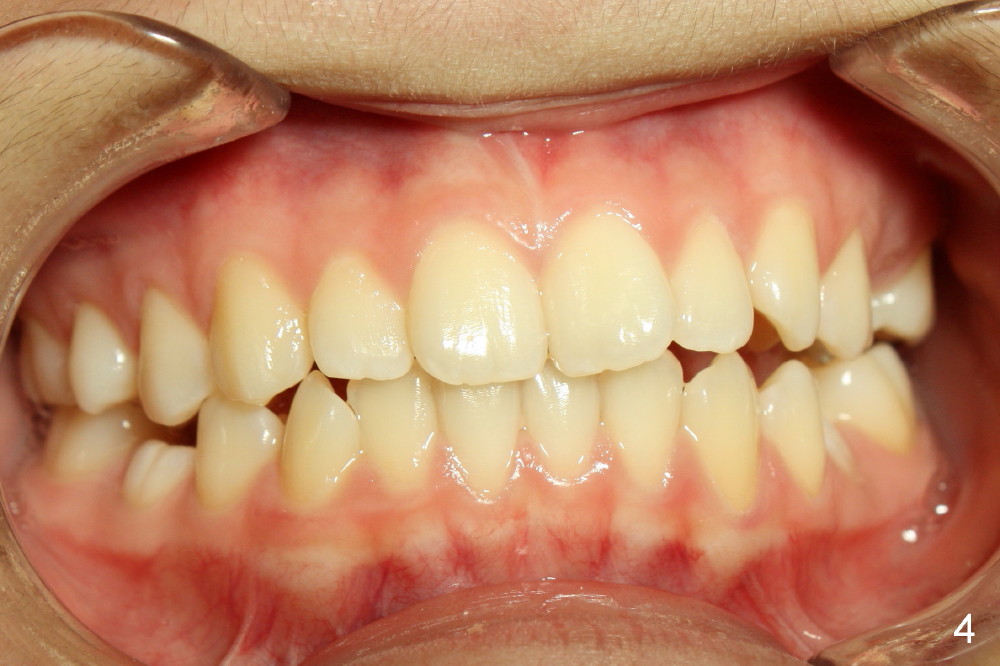

A 13-year-old Asian girl seeks orthodontic treatment for crowding. The lower 2nd bicuspids are congenitally missing (Fig.1,8), whereas the upper right one rotates 180° and the upper left is partially impacted (Fig. 1, 7). The lip muscles strain when the lips close (Fig.3). Orthodontic treatment started with extraction of four affected teeth (#4,13, K and T) 6 months ago. .018' niti wires are being used. Dental midlines do not coincide preop and intraop (Fig.4,4'). Pre-op front view shows that the upper dental midline coincides with the facial one (Fig.1'). There is Class I canine and molar relationship on the right (Fig.5,5',9,9'); open bite on the left (Fig.6,6',10,10').